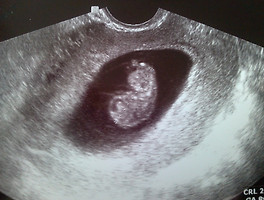

Doyeon& 도연이 Begins 2 of 2 뚱뚱보대장 2013. 7. 17. 공유하기 게시글 관리 DY Family 저작자표시 비영리 동일조건 (새창열림) 'Doyeon&' 관련글 생후 4주 생후 1주일 & 할아버지, 할머니 축하축하 꽃바구니 보민이 Begins 도연이 Begins 1 of 2 Notice 2017년 1월, 티스토리 초대장 나눔합니다.⋯ Archives Visits Today Yesterday